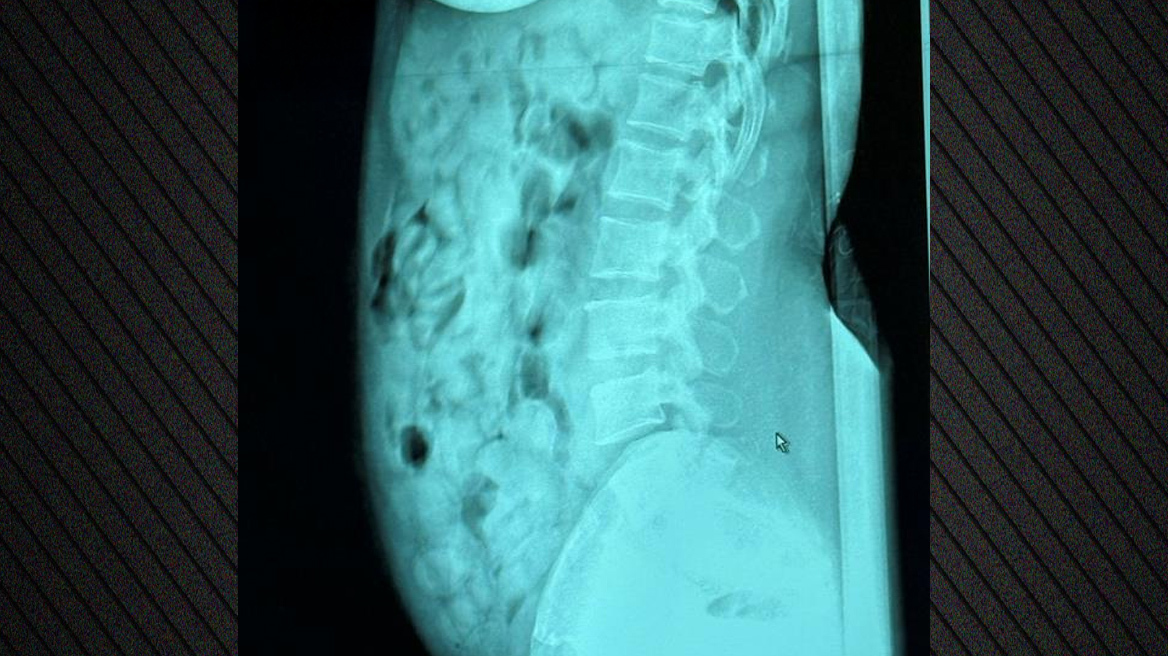

Στο αεροδρόμιο Orio al Serio του Μπέργκαμο της Ιταλίας, οι Αρχές συνέλαβαν επ’ αυτοφώρω μια 46χρονη γυναίκα από τη Νιγηρία, η οποία είχε καταπιεί 120 αμπούλες ηρωίνης συνολικού βάρους 1.393 γραμμαρίων.

Ακτινολογικές εξετάσεις στο νοσοκομείο του Μπέργκαμο επιβεβαίωσαν την παρουσία ναρκωτικών, τα οποία ήταν σφραγισμένα με κολλητική ταινία. Μετά την αποβολή τους, η ουσία κατασχέθηκε και η γυναίκα οδηγήθηκε στη φυλακή του Μπέργκαμο, στη διάθεση της δικαστικής αρχής.

Δείτε φωτογραφία: